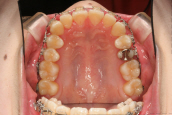

2015年4月2日から、矯正を開始しました。手術は行わず、原因である奥歯の高さの調整をして、同時に歯列の幅も広げました。ちょうど一年が経過しました。

2016年4月6日のお口です。歯は歯列におさまり、奥歯の噛み合わせも正常になっています。矯正治療は全ての歯を動かして並べ変える まさに「噛み合わせ治療」です。女性の平均寿命は85歳を越えています。これからの60年以上の時間 噛むことに耐えうる安定した状態を、歯を動かす矯正を利用して実現することを目標としています。